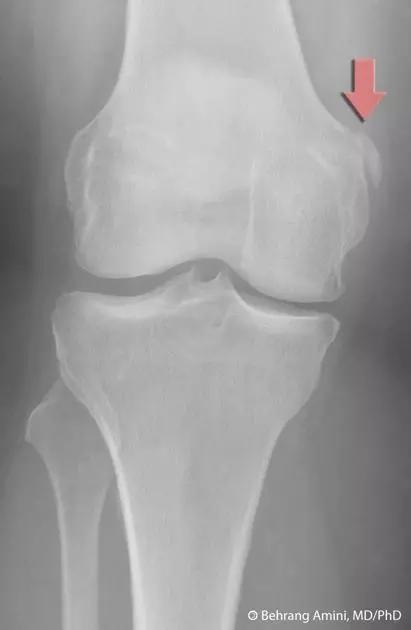

8. Segond 骨折和反向 Segond 骨折

(1)Segond 骨折

是发生在胫骨平台外侧的垂直撕脱性骨折。这种骨折在前后位 X 线片上显示最佳。屈曲位时膝关节受到内旋*力暴**作用,导致皮质骨撕脱性骨折,这种骨折常发生在运动员身上。

常引起股骨内髁和胫骨平台后内侧骨挫伤,75%~100% 的患者伴前交叉韧带断裂,33% 的患者伴外侧半月板损伤。

一位足球运动员的 Segond 骨折。A 正位片示关节线下方胫骨外侧皮质撕脱(箭头)。B MRI 冠状位 T1 加权像示附着于髂胫带的骨折碎片(空箭头)(来源:Radiol Clin N Am 53 (2015) 737–755,YU,Ohio)

(2)反向 Segond 骨折

胫骨平台内侧皮质骨撕脱性骨折,被称为内侧 Segond 骨折或反向 Segond 骨折。这种骨折的旋转机制与 Segond 骨折相反,该骨折与后交叉韧带断裂及内侧半月板损伤相关。

一位足球运动员的反向 Segond 骨折。A 正位片示关节线处的胫骨内侧见一细小骨折片(箭头)。B MRI 冠状位 T1 加权像示骨折片出现在内侧副韧带关节囊附着处(方框)(来源:Radiol Clin N Am 53 (2015) 737–755,YU,Ohio)